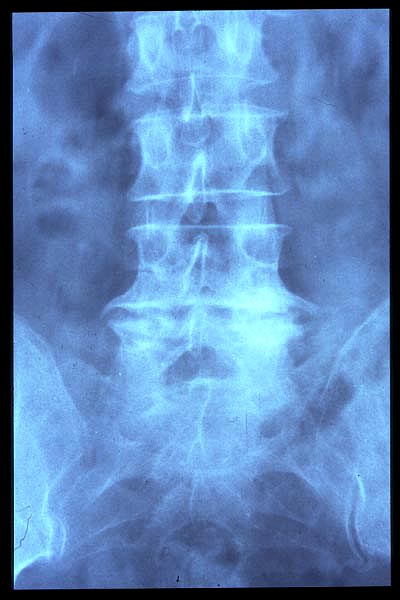

Artrosis lumbar con pinzamiento.

Artrosis lumbar